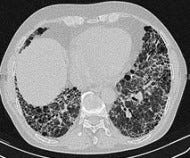

Pirfenidone prolongs survival, preserves lung function in idiopathic pulmonary fibrosis (ASCEND)

Pirfenidone reduced the decline of lung function, improved progression-free survival and prevented loss of exercise tolerance in people with idiopathic pulmonary fibrosis, as compared with placebo.

ASCEND enrolled 555 patients from 127 sites in 9 countries, mostly in the U.S. Subjects had clinical-radiographic or biopsy-confirmed IPF, and mild to moderate restrictive lung disease (forced vital capacity 50-90% predicted) along with diffusion impairment on pulmonary function testing. The CAPACITY enrollment criteria were tweaked for ASCEND to try to capture people at higher risk for disease progression (e.g., excluding those with comorbid COPD, and including more with worse diffusion impairments). They were randomized 1:1 to pirfenidone or placebo and followed for one year.